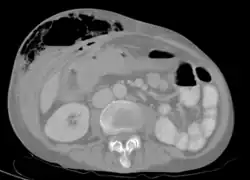

Abdominal CT scan with right colocutaneous fistula and associated subcutaneous pneumatosis | |

In anatomy, a fistula (pl.: fistulas or fistulae /-li, -laɪ/; from Latin fistula, "tube, pipe") is an abnormal connection (i.e. tube) joining two hollow spaces (technically, two epithelialized surfaces), such as blood vessels, intestines, or other hollow organs to each other, often resulting in an abnormal flow of fluid from one space to the other.[2][3][4] An anal fistula connects the anal canal to the perianal skin. An anovaginal or rectovaginal fistula is a hole joining the anus or rectum to the vagina. A colovaginal fistula joins the space in the colon to that in the vagina. A urinary tract fistula is an abnormal opening in the urinary tract or an abnormal connection between the urinary tract and another organ. An abnormal communication (i.e. hole or tube) between the bladder and the uterus is called a vesicouterine fistula, while if it is between the bladder and the vagina it is known as a vesicovaginal fistula, and if between the urethra and the vagina: a urethrovaginal fistula. When occurring between two parts of the intestine, it is known as an enteroenteral fistula, between the small intestine and the skin it is known as an enterocutaneous fistula, and between the colon and the skin as a colocutaneous fistula.[3]

Types of fistula can be described by their location. Anal fistulas connect between the epithelialized surface of the anal canal and the perianal skin. Anovaginal or rectovaginal fistulas occur when a hole develops between the anus or rectum and the vagina. Colovaginal fistulas occur between the colon and the vagina. Urinary tract fistulas are abnormal openings within the urinary tract or an abnormal connection between the urinary tract and another organ such as between the bladder and the uterus in a vesicouterine fistula, between the bladder and the vagina in a vesicovaginal fistula, and between the urethra and the vagina in urethrovaginal fistula. When occurring between two parts of the intestine, it is known as an enteroenteral fistula, between the small intestine and the skin as an enterocutaneous fistula, and between the small intestine and the colon as a colocutaneous fistula.[3]